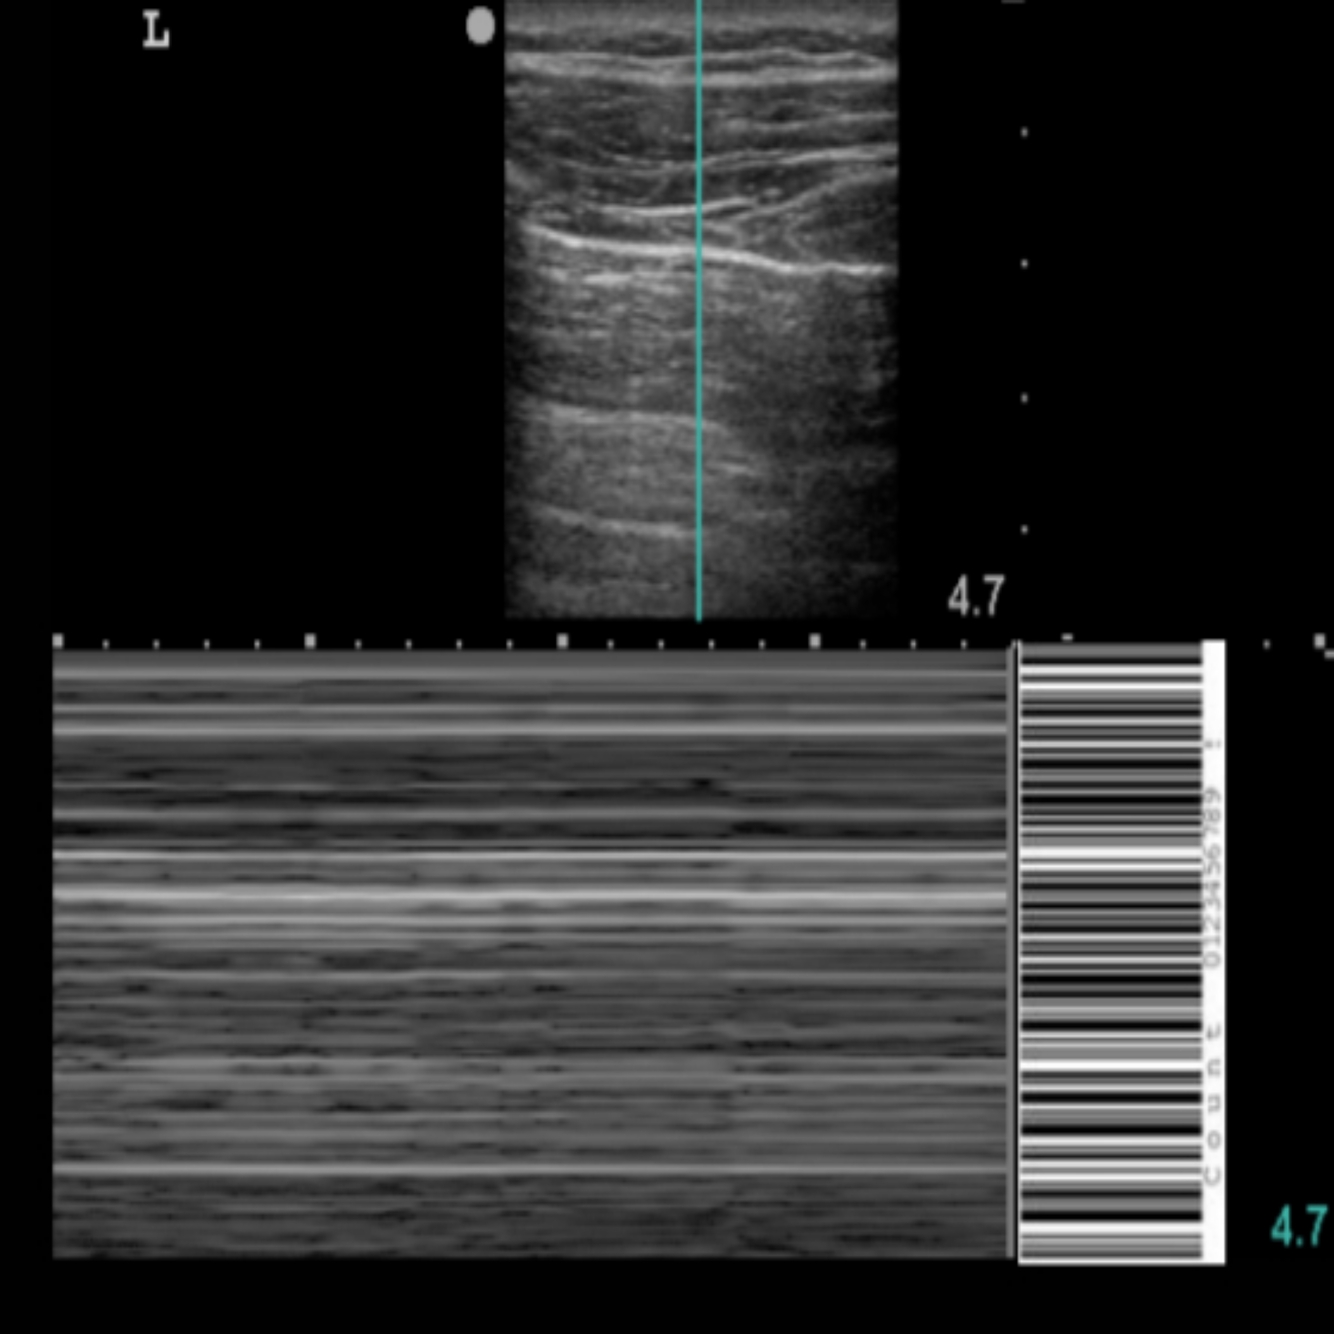

23

Q

POCUS PULMONAR: Qual o nome deste achado?

A

Sinal do código de barras

How well did you know this?

24

POCUS PULMONAR: Quando as pleuras não deslizam em feixe de ponto fixo é um sinal de

Código de barras